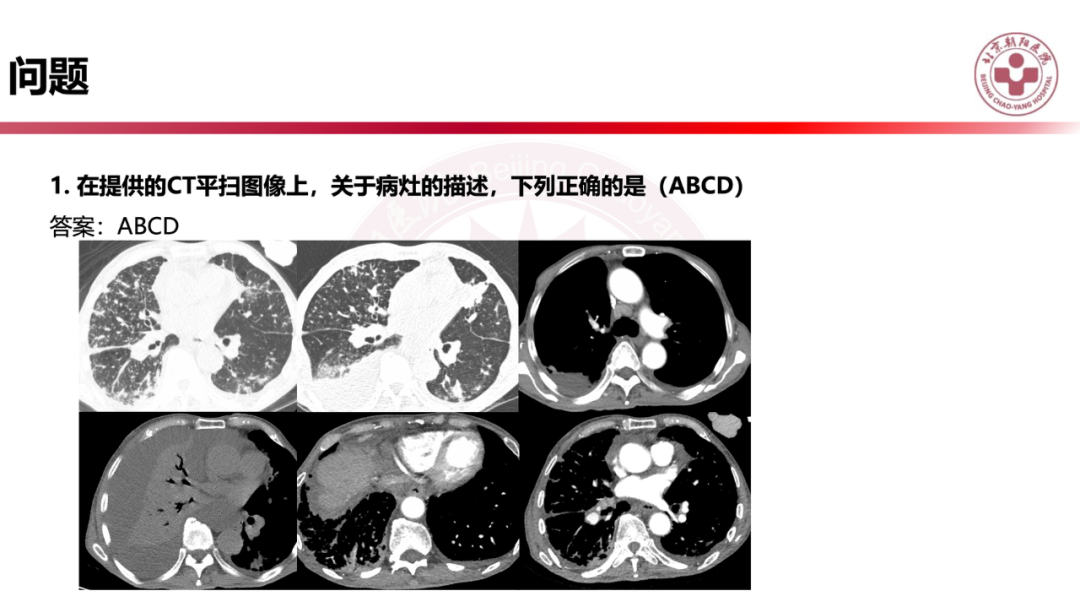

IgG4相关性肺疾病的诊断思路是什么?

来源:北京朝阳医院放射介入影像中心